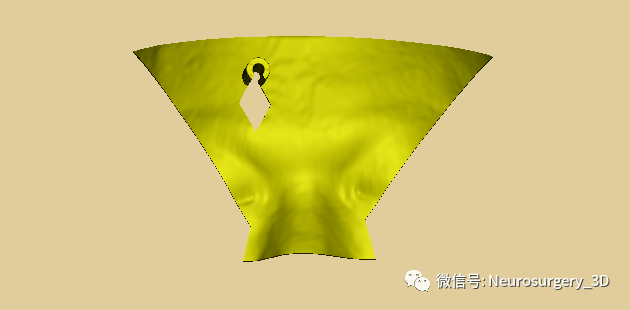

5、修剪需要打印的穿刺导板

8、由以上穿刺导板制作过程可以看出,穿刺导板应用Scissors小剪刀剪切修剪导板,其边缘并不规则,可把本节第四步生成穿刺导板面具后提前导出并保存于桌面上。